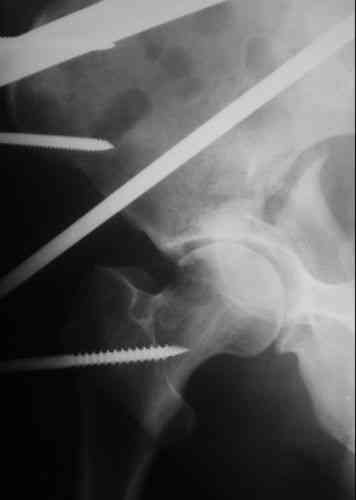

Пациентка 38 лет. В результате ДТП 02.09.06 получила поперечный перелом правой вертлужной впадины, центральный вывих правого бедра, разрыв правого крестцово-подвздошного сустава.

В одной из районных больниц вывих устранен, наложена система вытяжения по оси бедра и за вертельную область. Спустя 2 недели выполнен ВЧКО модулем "таз-бедро". Учитывая возраст пациентки и остаточный диастаз в области свода вертлужной впадины предполагается демонтаж аппарата, открытая репозиция и внутренний МОС вертлужной впадины через внутритазовый доступ.

Почему внутритазовый? Можно и из заднего доступа. Перелом достаточно простой.

У меня создалось впечатление( одна из РГ), что участок суставной поверхности нагрузочной зоны вертлужной впадины вдавлен( постарайтесь сделать КТ). Если это подтвердиться, то из внутритазового доступа отрепонировать будет невозможно.